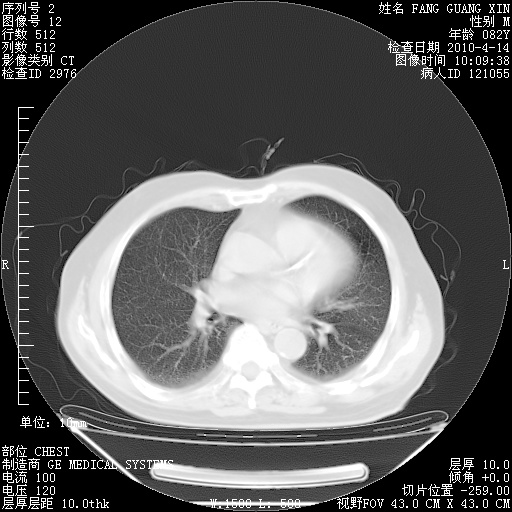

4月14日肺部CT

肺部CT平扫未见异常。